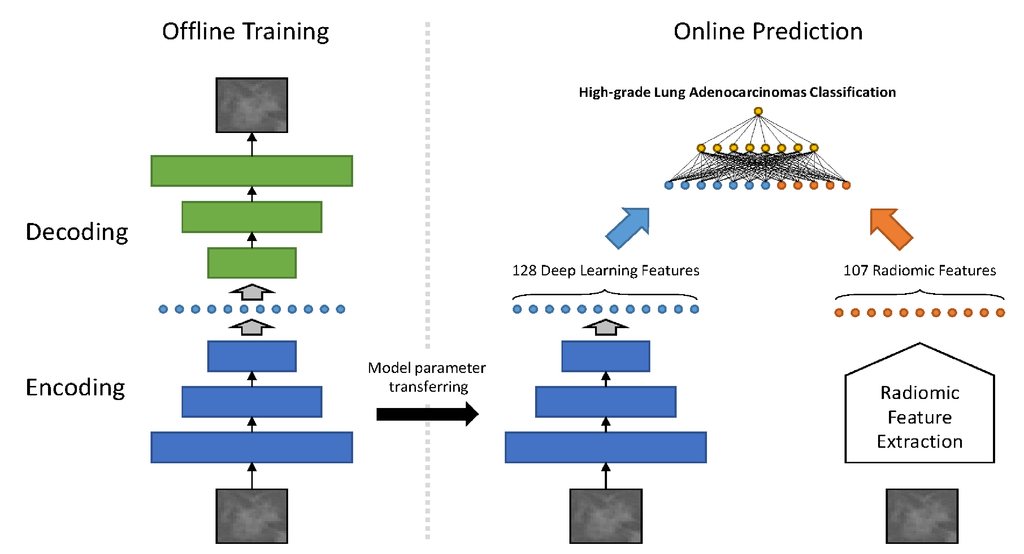

Adenocarcinoma (ADC) is the most common histological subtype of lung cancers in non small cell lung cancer (NSCLC) in which ground glass opacifications (GGOs) found on computed tomography (CT) scans are the most common lesions. These lesions are usually treated with limited lung resection. However, the presence of a micropapillary or solid component is identified as an independent predictor of prognosis, indicating a more extensive resection. The accurate classification of subtypes still remains difficult in radiology or in frozen pathological analysis, even with the help of classical radiomics. The purpose of our study is to explore imaging phenotyping using a novel method combining radiomics with deep learning (RDL) to predict high-grade patterns within lung ADC.

Included in this study were 111 patients differentiated as having GGOs and pathologically confirmed ADC. Four different methods were compared to classify the GGOs for the prediction of the pathological subtypes of high-grade lung ADCs, including classic machine learning, radiomics, deep learning method, and a proposed novel method referred as RDL. A four-fold cross-validation approach was used to evaluate the performance of such methods.

We analyzed 32 patients with high-grade patterns and 79 without such patterns. The proposed RDL has achieved an overall accuracy of 0.888, which significantly outperforms classic machine learning, radiomics, and deep learning alone (p< 0.001, paired t-test).

High-grade lung ADC based on histologic pattern spectrum in GGO lesions might be predicted by a novel framework combining radiomics with deep learning, which reveals a significant advantage over traditional methods.